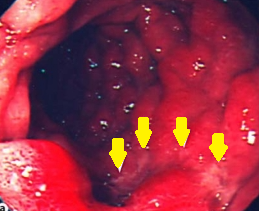

Duodenoscopy. Yellow arrows – Incipient ischemic changes of the third portion of the duodenum due to pressure from the obstruction. Courtesy Dr. V. Penopoulos.